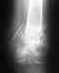

02.август.2010 г. - Травма получена в результате ДТП. Пациентка была доставлена в Городскую больницу №4. Диагноз при поступлении: закрытый оскольчатый внутрисуставной перелом лучевой кости левого предплечья в типичном месте со смещением; закрытый прелом обеих лодыжек левой голени со смещением и разрывом ДМС, полный вывих стопы; закрытый перелом наружного мыщелка большеберцовой кости левой голени без смещения. Была произведена репозиция отломков с наложением гипсовых повязок.

09.август.2010 г. - На контрольных рентгенограммах определялось смещение отломков лодыжек левой голени. Показана операция.

Диагноз на сегодняшний день на основании рентгенограмм, КТ (23.ноябрь.2011 г.), МРТ (06.сентябрь. 2011 г.): сросшийся перелом обеих лодыжек левой голени с формированием латерального подвывиха таранной кости. Неоартроз в суставе медиальной лодыжки с признаками асептического остеонекроза эпиметафиза большеберцовой кости и медиального суставного края таранной кости.